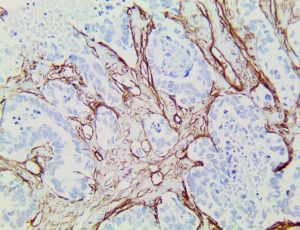

This activation induces inflammatory monocytes to highly express IL-6, starting a localized and then systemic cascade effect that results in hyperproduction of IL-6, which accelerates the inflammatory process. Because IL-6 also increases vascular permeability, excessive levels cause blood vessels to become very leaky. This, along with clotting factors released from vascular endothelial cells, stimulates the coagulation cascade, resulting in microthrombosis (tiny clots), which leads to ischemia and tissue death of the kidney, intestines, heart, liver, brain and extremities.